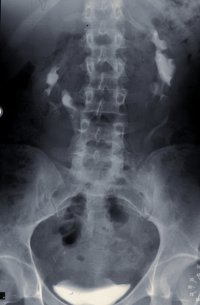

Im Ausscheidungsurogramm und im CT war eine Hufeisenniere mit Pyelektasie links zu erkennen (Abbildung 5).